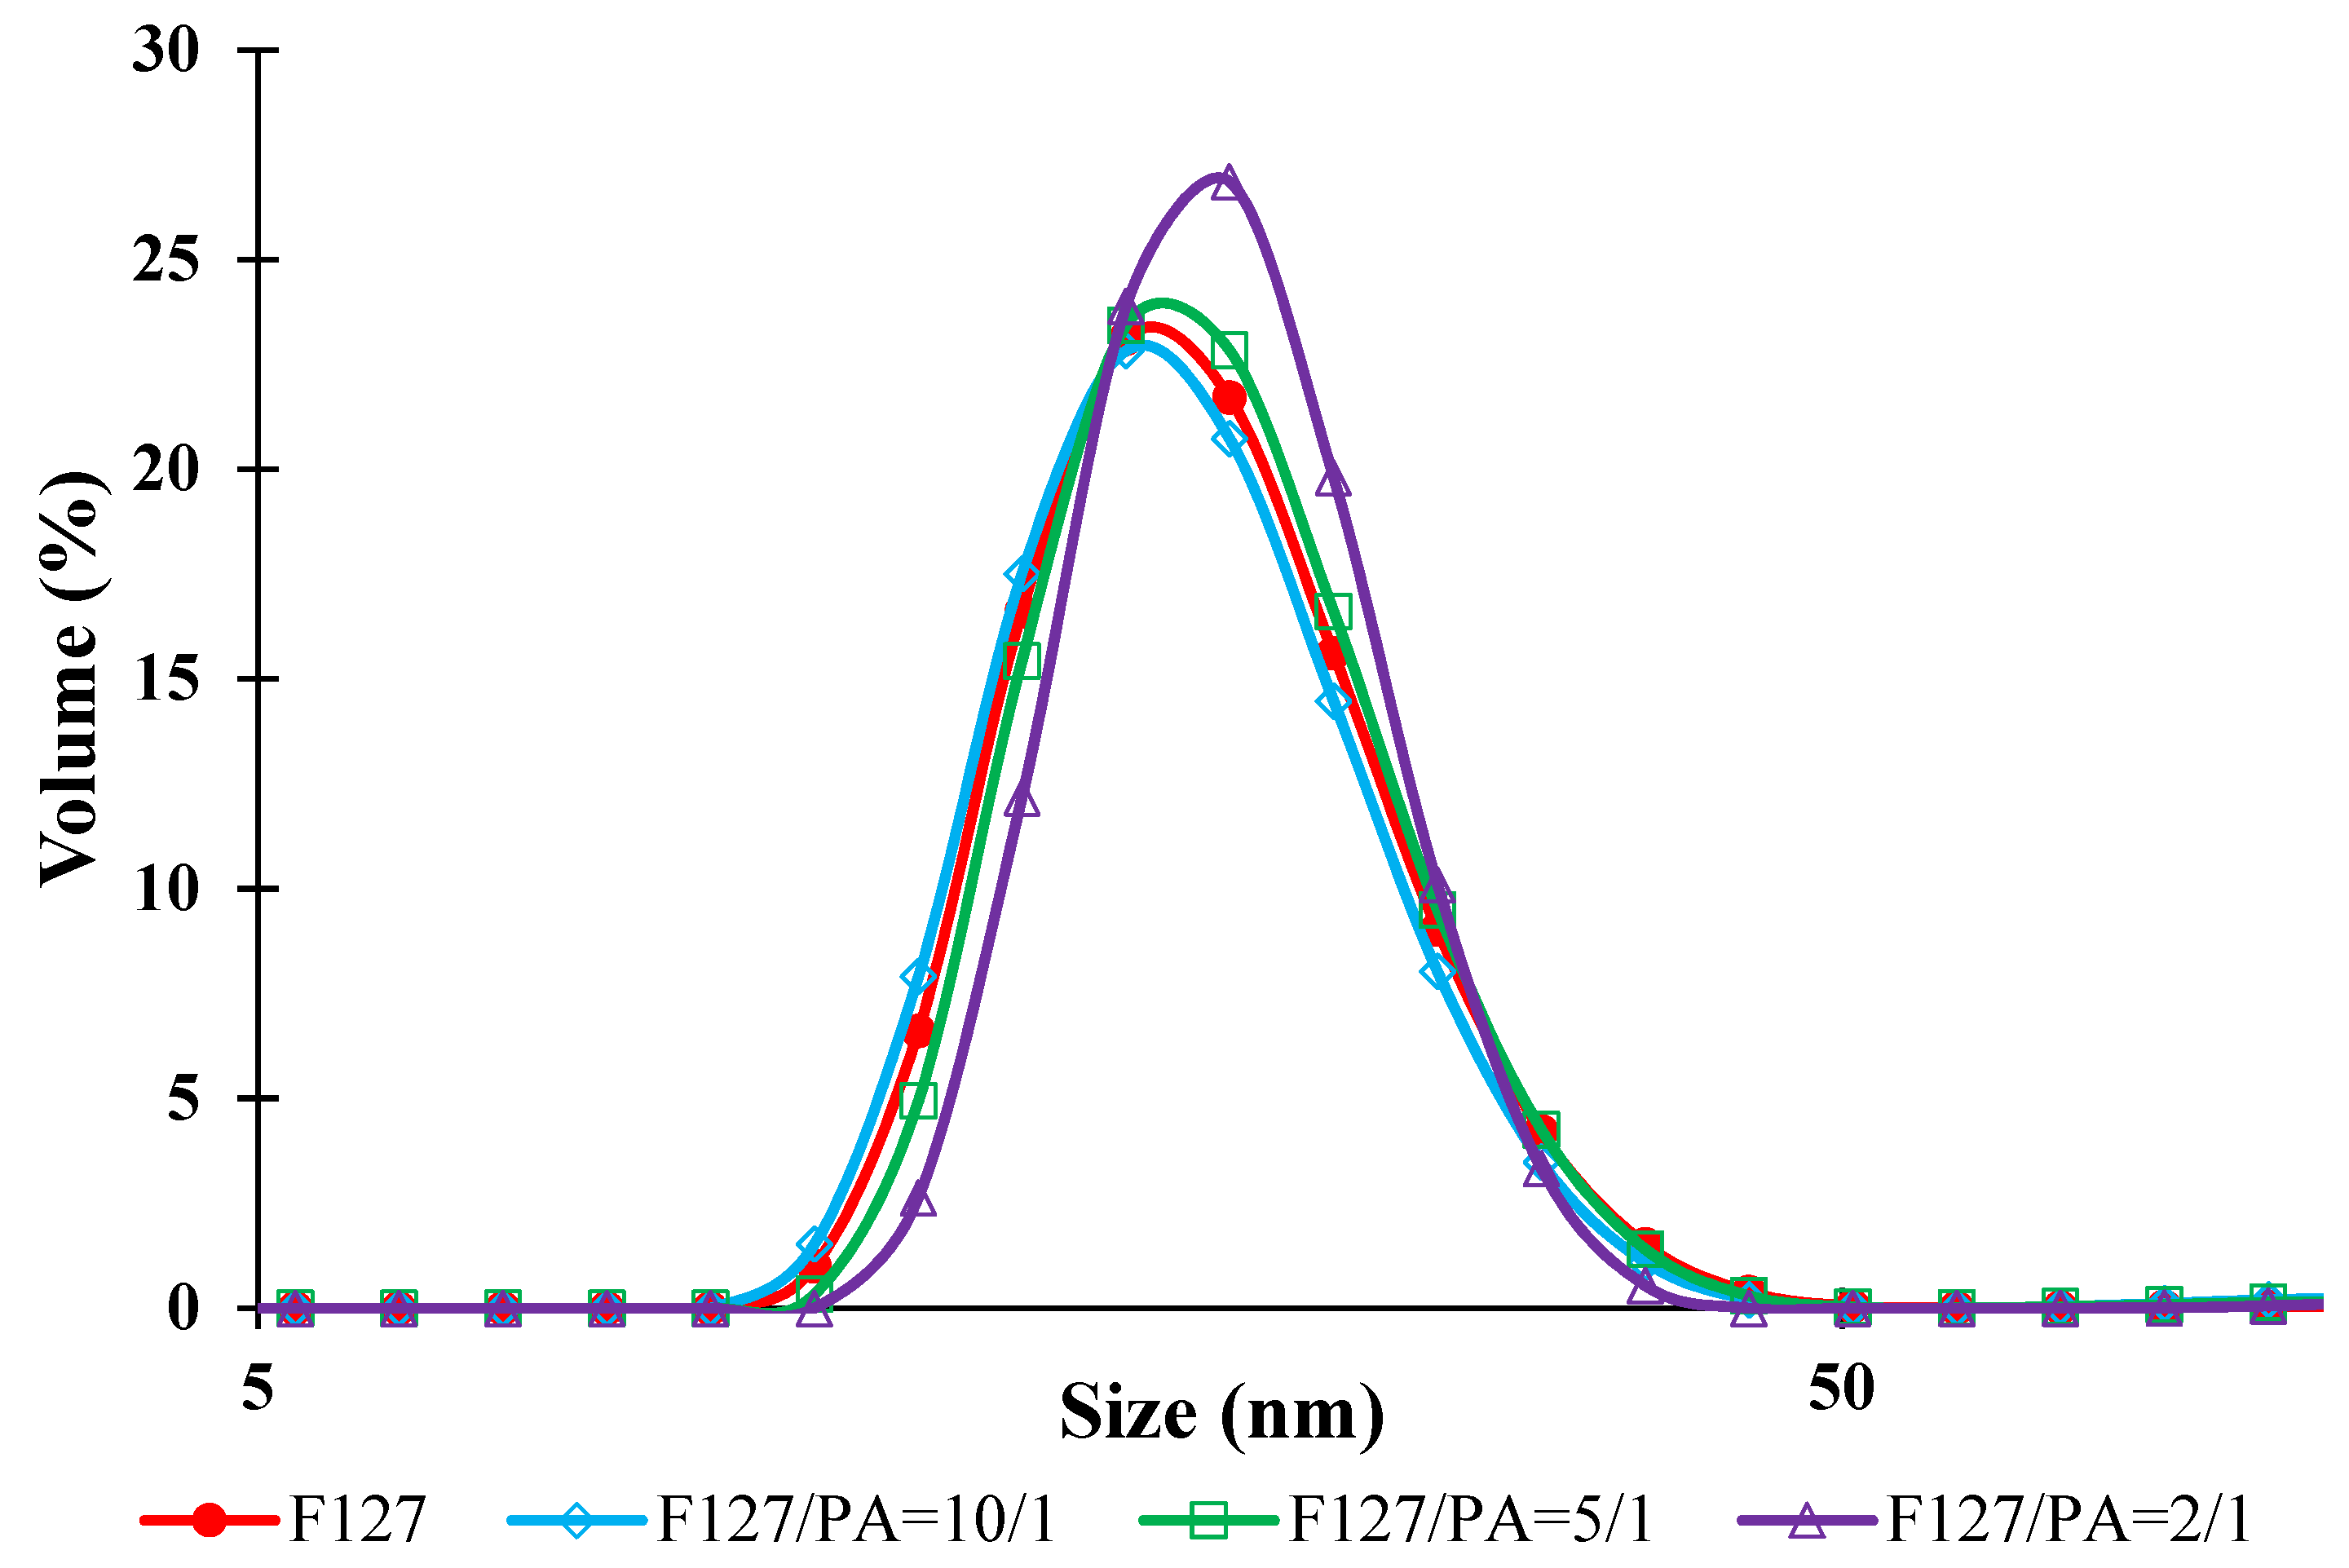

3.1. Micellar Sizes and Stability

| Sample | Dv (nm) | PDI | ZP (mV) |

|---|---|---|---|

| F127 | 20.3 ± 0.1 | 0.141 | −3.0 |

| F127/API= 10/1 (% w/w) | 20.7 ± 0.2 | 0.198 | −3.0 |

| F127/API= 5/1 (% w/w) | 20.3 ± 0.2 | 0.284 | −2.8 |

| F127/API = 2/1 (% w/w) | 21.4 ± 0.3 | 0.308 | −2.7 |